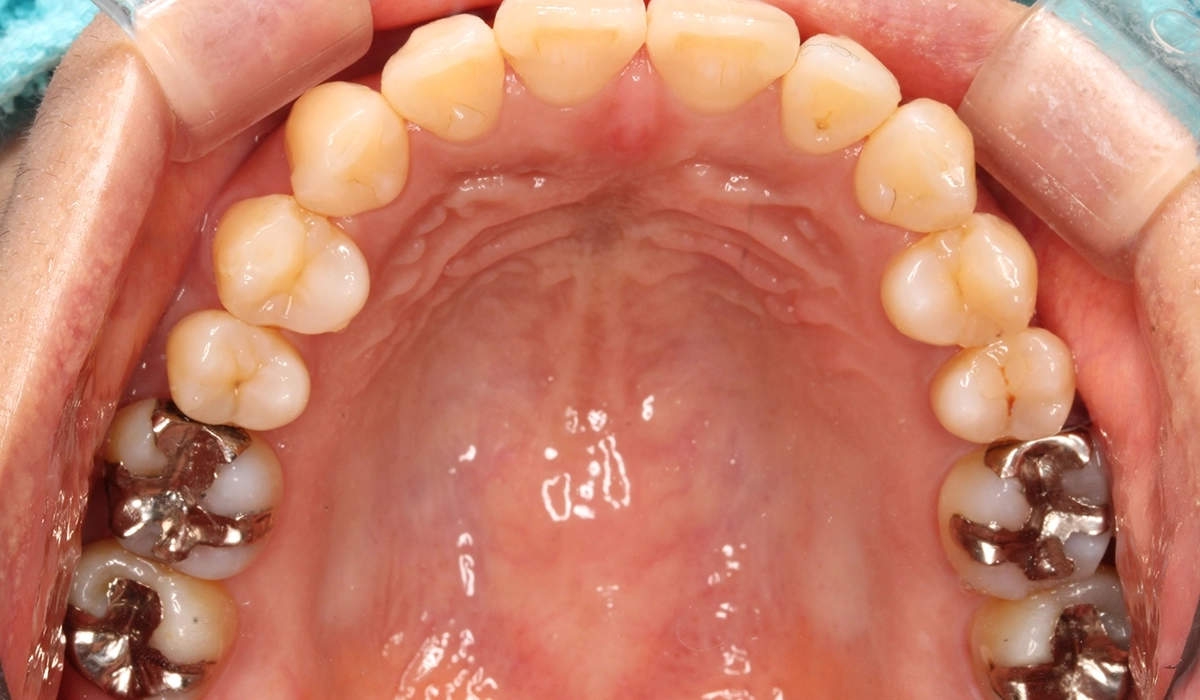

術前:上顎

術後:上顎